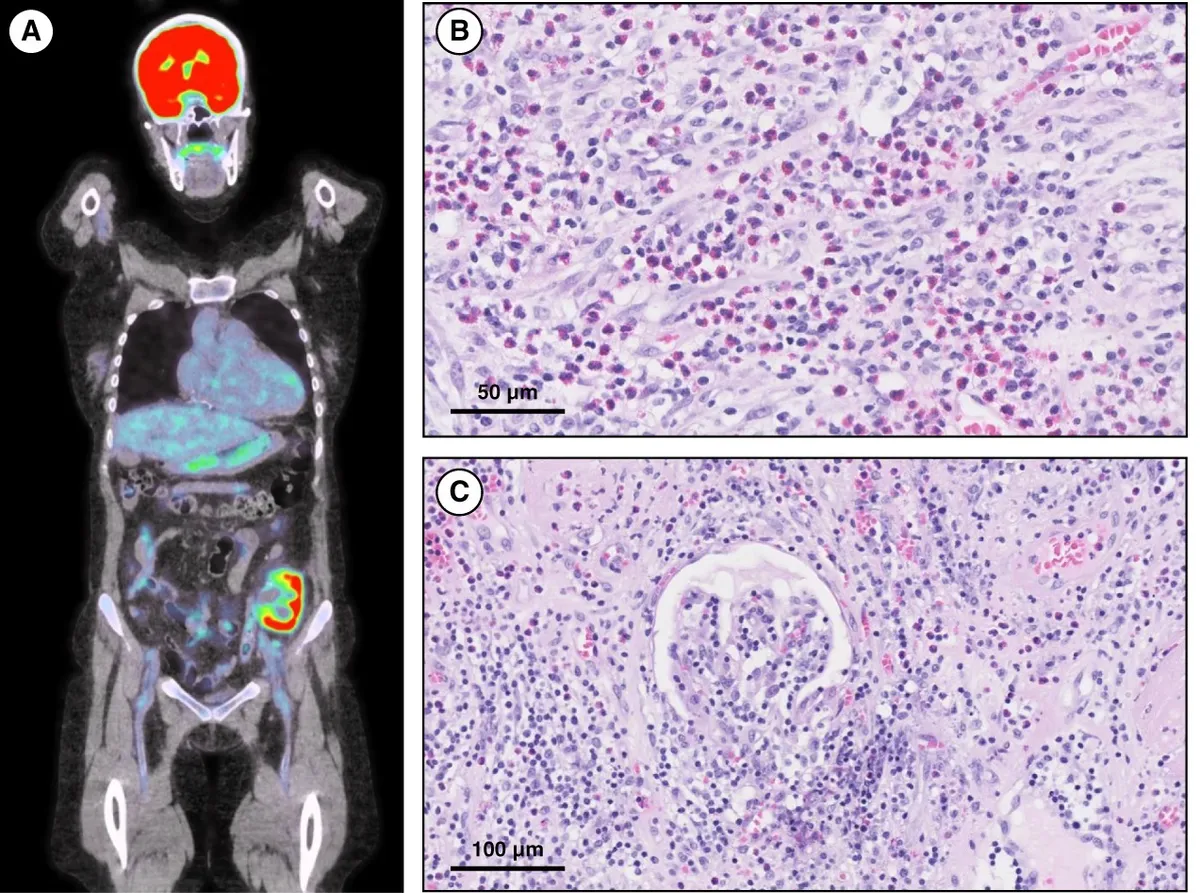

Uma causa incomum de hematúria glomerular intermitente!

Hematúria pós infecção, caso clínicos para auxiliar no entendimento de causas glomerulares comuns e raras...